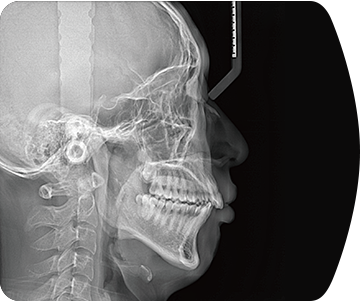

标配专业正畸软件

支持自动描点功能

精准定位

临床样片